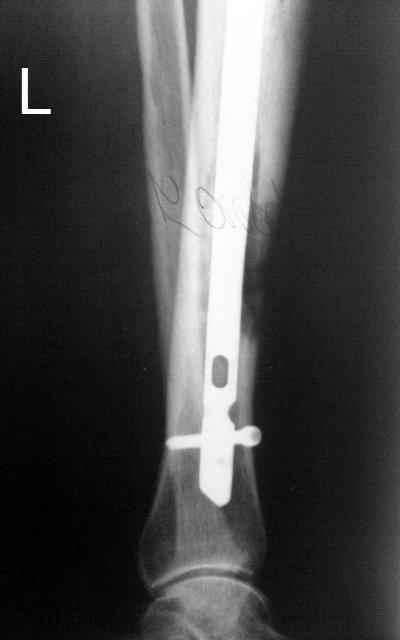

Итак, в настоящий момент больной пришел к нам с полной нагрузкой на оперированную конечность и с такой картиной (см. приложение). Участок мягких тканей с передней стенкой нижней трети ББК, выгнил и представляет дефект 2×2,5 см. На перевязке - циркулярный(?) некроз костной трубки.

Пациенту за 70 лет. Мои соображения: 1 этап - резекция tibia + косая остеотомия fibula + «острое» укорочение + IM цемент-гвоздь с а/б + beads. 2 этап (по заживлению раны) – удаление цемент-гвоздя + (LATN) Lengthening and Then Nailing. Прошу помощи по тактике.Никита Заднепровский

Сегментарного некроза не видно. Есть только краевой дефект спереди, задняя стенка вполне хорошая, и со стержнем есть условия для ее утолщения со временем. Так что проблему должна решить местная санация (если доступно, использовать VAC). Если грануляции не закроют все, что надо закрыть, придется делать пластику полнослойным лоскутом. Идеально бы - с микроососудистым анастомозом.